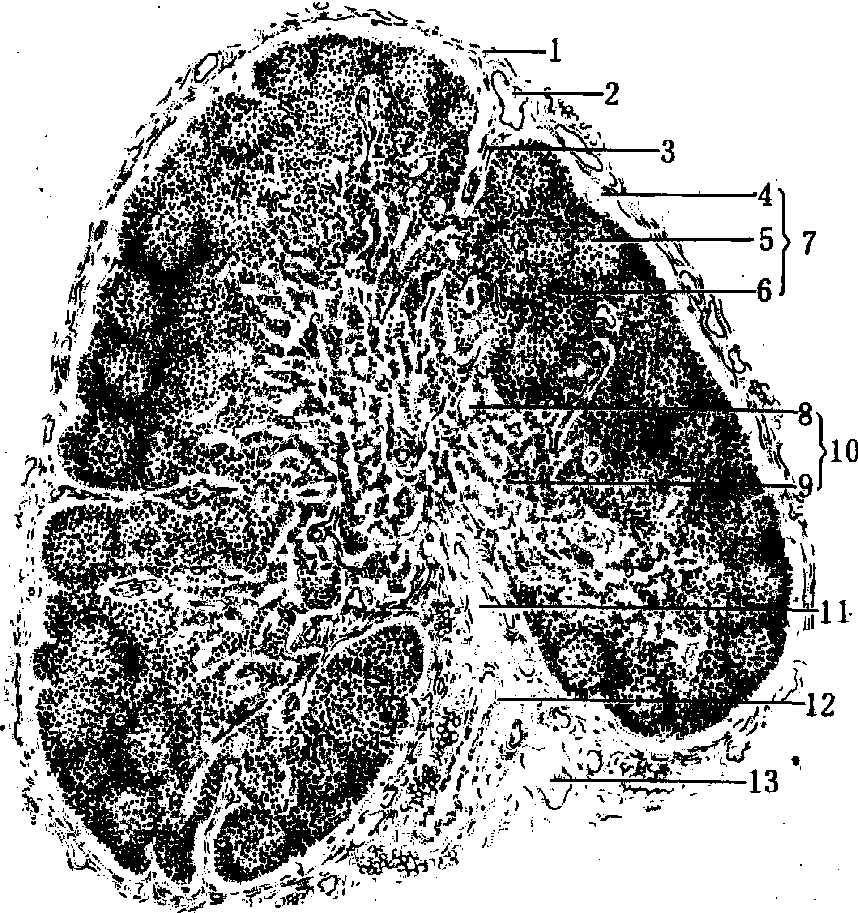

淋巴结是以淋巴组织和淋巴窦为主组成的器官,人约有400个,呈豆形或卵圆形,大小不等,直径约1~25mm,多成群分布于肠系膜、肺门、腹股沟和腋窝等处。淋巴结位于淋巴管回流的中途,有几条输入淋巴管通入结内的淋巴窦,淋巴窦再汇成1~2条输出淋巴管,由淋巴结的门导出。淋巴结的实质由淋巴组织和淋巴窦组成(图1),分皮质和髓质。不同部位和不同免疫状态下,淋巴结的淋巴组织有很大的差别。淋巴结的功能是滤过淋巴和对抗原产生免疫应答。

图1 淋巴结的结构(光镜)

1.被膜 2.淋巴小结 3.输入淋巴管 4.副皮质区 5.髓索 6.小梁 7.髓索 8.被膜下淋巴窦 9.输出淋巴管 10.门 11.血管

淋巴结的结构 淋巴结表面有薄层致密结缔组织组成的被膜,有数条输入淋巴管穿过被膜进入结内。淋巴结的一侧凹陷,有较多的结缔组织,并有输出淋巴管、血管和神经经此出入,称为门。被膜及门的结缔组织伸入实质形成相互连接的粗网状支架,称为小梁。小梁间又有网状组织(参见“网状组织”条)形成微细的支架。淋巴结的实质分皮质和髓质,皮质在淋巴结的周边,髓质在淋巴结的内部。皮质和髓质都由淋巴组织和淋巴窦组成。

(2)深层皮质单位:又称副皮质区。每个单位为半球形,平的一侧对着一条输入淋巴管,位于一群淋巴小结的内侧(图2)。另一侧凸向髓质。如二条输入淋巴管的入口靠近,则其下的二个单位可融合为一个较大的复合体。深层皮质单位的数目与淋巴结的大小和输入淋巴管的数目成正比。每个单位可分中央区和周围区。中央区由密集的小淋巴细胞构成,含T细胞,为胸腺依赖区。新生鼠去胸腺后此区T细胞很少。受抗原刺激引起细胞免疫应答时,此区变大,淋巴细胞增多,有丝分裂象增多,交错突细胞增多,以致形成T小结,可产生大量T记忆细胞和T效应细胞。周围区为一薄层较疏松的淋巴组织,含有T和B细胞,位于中央区与髓质之间。由于中央区含网状纤维少而周围区明显增多,故二者之间有明显的界限。周围区含许多毛细血管后微静脉和一些小的淋巴窦(图2)。淋巴结的毛细血管后微静脉起于浅层小结外区,穿越深层皮质中央区到达周围区,直径约40μm,内皮呈立方形,可见淋巴细胞穿过内皮。血管周围有较多的巨噬细胞。血流经此处时约有1/10的淋巴细胞进入此区,也有少量的淋巴细胞由淋巴组织经毛细血管后微静脉进入血流。周围区的淋巴窦始于盲端,较髓窦小,腔内不含网状细胞,而有由淋巴组织穿越血管内皮进入的许多中、小淋巴细胞。故周围区淋巴细胞的迁移较快。

图2 深层皮质单位立体结构模式图

1.被膜下淋巴窦 2.深层皮质中央区 3.被膜 4.输入淋巴管 5.小结外区 6.帽 7.明区 8.深层皮质周围区 9.小淋巴窦 10.毛细血管后微静脉 11.髓质淋巴窦 12.髓索 13.暗区